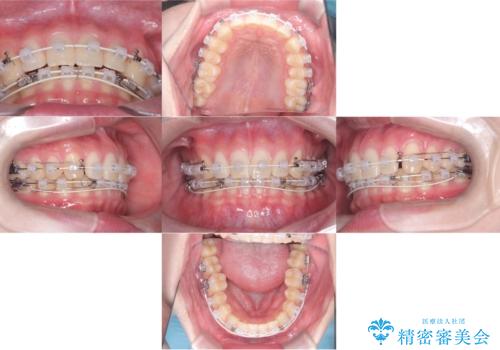

【ワイヤー矯正】すきっ歯を治したい

- 主訴:上の前歯のすきっ歯を治したい。

今回のような空隙歯列に対したは、マウスピース矯正・ワイヤー矯正どちらの方法でも矯正治療可能と説明し、ワイヤー矯正を希望されました。

上顎中切歯間の隙間の他にもフロスが抵抗なく入るスペースが上顎は数か所ありました。スペースを閉じ下顎の歯列弓との調和をとるためIPRを行いました。

下顎の舌側傾斜気味の前歯も唇側へ歯軸傾斜させています。

矯正期間:1年2か月